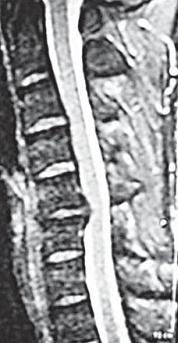

На МРТ № 18 наблюдаются грыжи межпозвонковых дисков в сегментах: — LIV-LV вентральной локализации с образованием каудального секвестра; при расположении межпозвонковой грыжи на один сегмент выше, «конфликт» с брюшной аортой был бы неизбежен; — LV-SI — дорсальная грыжа межпозвонкового диска, частично компенсированная спондилёзом МРТ № 19 ![]() МРТ № 20 ![]() На МРТ № 19 наблюдается дорсальная грыжа межпозвонкового диска шейного отдела позвоночника в сегменте СV-СVI с компрессией спинного мозга На МРТ № 20 наблюдается грыжа межпозвонкового диска шейного отдела позвоночника в сегменте CV—CVI и протрузия в сегменте CVI-CVII Замечу, что если грыжа межпозвонкового диска имеет достаточно большой размер и локализована в шейном отделе, то она способна вызвать не только соматические нарушения, но и даже психические расстройства. Причина кроется в сдавлении дурального мешка грыжей межпозвонкового диска (дуральный мешок — это герметичный соединительнотканный мешок, формируемый твёрдой мозговой оболочкой, в котором расположен спинной мозг). Как известно, спинной мозг не имеет болевых рецепторов. Однако вышеуказанная патология приводит к локальному устойчивому возбуждению определённых зон коры головного мозга. На субъективном уровне это может проявляться как постоянное чувство тревоги (так называемый «синдром ожидания»). Грыжи межпозвонковых дисков в грудном отделе позвоночника явление довольно редкое, но всё же наиболее опасное. Опасное потому, что эпидуральное пространство в грудном отделе позвоночника узкое по сравнению с другими отделами, в пределах всего 0,2–0,4 см по всей окружности дурального мешка (твёрдой оболочки спинного мозга). Поэтому даже небольшое грыжевое выпячивание может сдавить спинной мозг и вызвать тяжелейшие осложнения. Но, как уже говорилось, это явление в грудном отделе позвоночника редкое, поскольку высота межпозвонковых дисков довольно мала, всего около 3–5 мм, да и грудной отдел позвоночника менее подвижен по сравнению с другими отделами за счёт жёсткого рёберного каркаса, а значит, менее подвержен травматизации. МРТ № 21